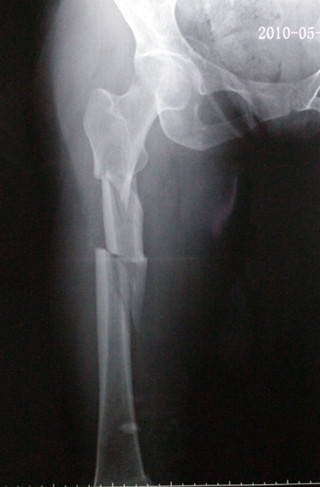

股骨干复杂骨折